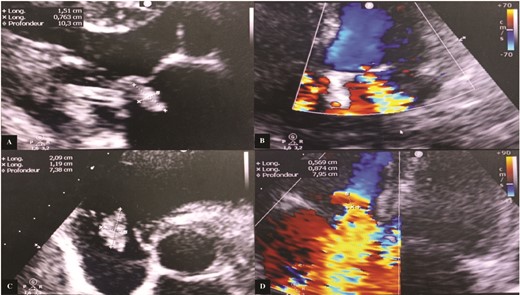

Transthoracic echocardiography (TTE) revealed a mitral valve with moderate, eccentric, double-jet regurgitation, perforation of the anterior mitral leaflet, and the presence of vegetation on the atrial side of the anterior mitral leaflet, which was pedicled, mobile, and measuring 15 × 7.6 mm. The tricuspid valve had vegetation interfering with valve closure, measuring 21 × 12 mm, causing significant central tricuspid regurgitation, with a systolic pulmonary artery pressure (SPAP) at 64 mmHg (Fig. 1).

Transthoracic echocardiography images. (A) Vegetation attached to the atrial side of the anterior mitral leaflet measuring 15 × 7.6 mm. (B) Significant mitral regurgitation. (C) Vegetation attached to the free edge of the anterior tricuspid leaflet measuring 21 × 12 mm. (D) Massive tricuspid regurgitation.